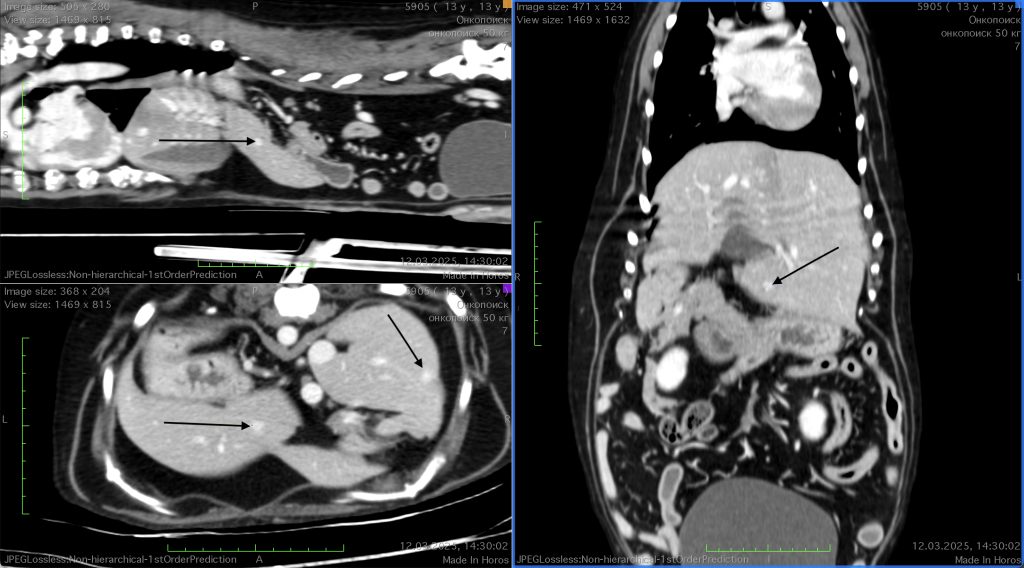

На фоне отмены доксорубицина и вынужденного отказа от протокола VAC, КТ от 25.12.2024 показала отрицательную динамику: увеличение объема и количества метастатических очагов в печени (фото 4).

Контрольное КТ-исследование, проведенное 12.03.2025 после двух введений ЛД (фото 5), продемонстрировало выраженную положительную динамику: в печени наблюдалось уменьшение объема и количества метастатических очагов по сравнению с результатами предыдущего исследования от 25.12.2024 (фото 4).Таким образом, было документально подтверждено начало частичной ремиссии на фоне терапии, которая поддерживалась за счет регулярных (каждый 21 день) введений ЛД, что также было подтверждено контрольным КТ-исследованием, проведенным 05.07.2025 (фото 6).